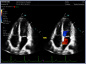

Neben einem ausführlichen Gespräch, der Anamnese, Zeit und Zuwendung gehören auch die Anwendung von wissenschaftlich evaulierten diagnostischen Verfahren zu einer guten Eingangsuntersuchung. Ich freue mich Ihnen in meiner Praxis deshalb nun auch die Ultraschalluntersuchung mit modernster Technik, einem mindray Consona N6 anbieten zu können.

- Darstellung der Schilddrüse - Darstellung der hirnversorgenden Gefäße mit Messung der Intimadicke (IMD) - Ultraschall des Herzens z. B. Stenose / Dichtigkeit der Herzklappen, Wandbewegungsstörungen,... - Ultraschall des Bauchraumes wie Leber, Gallenblase, Nieren, Blase, Milz. - Gefäßdarstellung

Video Farbdoppler der Halsarterie zur Darstellung der Durchblutung Video Farbdoppler der Niere zur Darstellung der Durchblutung Video Herzultraschall eines gesundes Herzens mit guter Pumpfunktion Video Herzultraschall mit eingeschränkter Pumpfunktion und vergrößerten Vorhöfen Video Herzultraschall bei Herzinsuffizienz und undichter Herzklappe